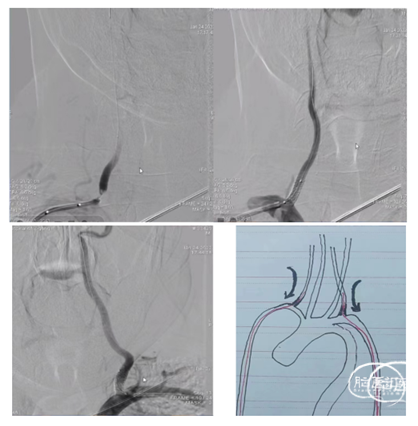

(二)高位椎动脉狭窄经绕同侧入路椎动脉狭窄支架置入

1、椎动脉狭窄,如果开口向外侧,行同侧桡动脉入路时角度顺行,可选择同侧桡动脉置入6F动脉鞘,0.035泥鳅导丝置于病灶侧锁骨下动脉起到或单弯同轴将6F导引导管到达狭窄椎动脉附近,微导丝导引球囊扩张支架(4-5mm)铆定狭窄部位后扩张释放支架。

1、双侧桡动脉置入6F动脉鞘。健侧进行造影定位和观察。

患侧将0.035in泥鳅导丝通过狭窄进行小球囊扩张(3-3.5mm)建立通路,撤出球囊。

沿泥鳅导丝(不用导引导管)将7-10mm球扩支架到位,通过对侧造影铆定后球囊扩张释放。

2、输送7-10mm球扩支架时不需要导引导管,直接沿泥鳅导丝输送,球扩支架不释放时小于2.5mm,能够顺利通过桡动脉。